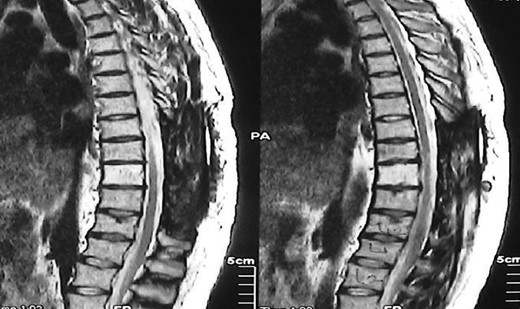

A 30-year-old male patient was admitted to our clinic with back pain. Pain was provoked by movements. The severity of pain was associated with the inability to perform the activities of daily living. The patient did not have any lymphoma-related B-type symptoms, including body weight loss, fever and sweat at night. He did not have a past and family history. There was no neurological deficit. Routine laboratory test results were normal. A magnetic resonance imaging (MRI) scan of the thoracic spine demonstrated an epidural tumor at the T9–11 level (Figs 1–3). The patient underwent spinal cord decompression via total laminectomy of T9–11 levels. Subtotal resection of the tumor was performed. Histological examination revealed the polymorphous cellular infiltration by histiocytes, large mononuclear cells and lacunar Reed–Sternberg cells with folded multi-lobed nuclei and small nucleoli (Fig. 4). Immunohistochemical staining was positive for CD15 and CD30 and negative for CD3, CD20, CD79a or CD45Ro. These features were most frequently observed in the mixed cellularity type of Hodgkin's lymphoma. Histological examination of the vertrebral body revealed no abnormality. The results of all other examinations (F-18 fluorodeoxyglucose positron emission tomography (F-18 FDG PET/CT), bone marrow biopsy and computed tomography (CT) of the chest, abdomen and pelvis) were negative for an occult disease. The patient was referred to the hematology department to undergo staged treatment. Six courses of chemotheraphy containing ABVD regimen (adriamycin, bleomycin, vinblastine and dacarbazine) were given to the patient. Postoperative MRI scan did not reveal any evidence of Hodgkin's disease (Fig. 5), F-18 FDG PET/CT, CT of the chest, abdomen and pelvis were obtained in 24 months and did not reveal any evidence of Hodgkin's disease.

Postoperative MRI scan did not reveal any evidence of Hodgkin's disease.